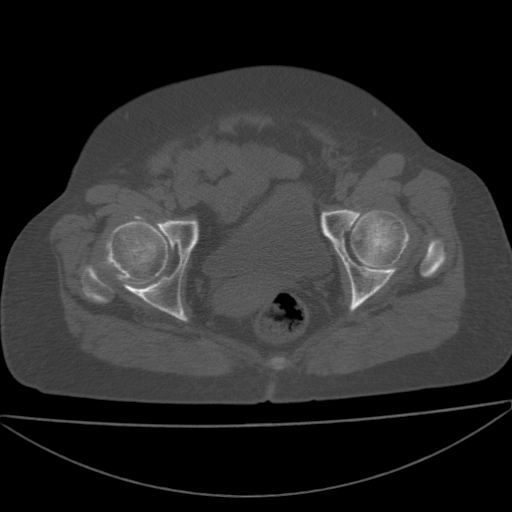

以下是引用余辉在2009-4-23 17:08:00的发言:[br]考虑右髋关节退行性变.股骨颈改变考虑陈旧性骨折可能,股骨头顶部关节面下似有透亮区,股骨头皮质环增厚,考虑有股骨头坏死

以下是引用王显瑞在2009-4-23 16:45:00的发言:[br]考虑股骨颈陈旧性骨折,股骨头缺血型坏死